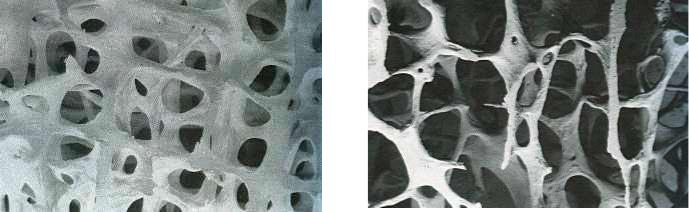

Развитие костной ткани

Развитие кости из мезенхимы (эндомембранный остеогенез) – прямой остеогенез.

Развитие кости на месте гиалинового хряща (эндохондральный остеогенез) – непрямой остеогенез